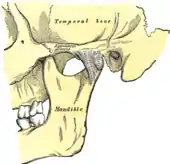

Left temporomandibular joint, lateral view.

The temporomandibular joints are the dual articulation of the mandible with the skull. Each TMJ is classed as a "ginglymoarthrodial" joint since it is both a ginglymus (hinging joint) and an arthrodial (sliding) joint,[36] and involves the condylar process of the mandible below, and the articular fossa (or glenoid fossa) of the temporal bone above. Between these articular surfaces is the articular disc (or meniscus), which is a biconcave, transversely oval disc composed of dense fibrous connective tissue. Each TMJ is covered by a fibrous capsule. There are tight fibers connecting the mandible to the disc, and loose fibers which connect the disc to the temporal bone, meaning there are in effect 2 joint capsules, creating an upper joint space and a lower joint space, with the articular disc in between. The synovial membrane of the TMJ lines the inside of the fibrous capsule apart from the articular surfaces and the disc. This membrane secretes synovial fluid, which is both a lubricant to fill the joint spaces, and a means to convey nutrients to the tissues inside the joint. Behind the disc is loose vascular tissue termed the "bilaminar region" which serves as a posterior attachment for the disc and also fills with blood to fill the space created when the head of the condyle translates down the articular eminence.[37] Due to its concave shape, sometimes the articular disc is described as having an anterior band, intermediate zone and a posterior band.[38] When the mouth is opened, the initial movement of the mandibular condyle is rotational, and this involves mainly the lower joint space, and when the mouth is opened further, the movement of the condyle is translational, involving mainly the upper joint space.[39] This translation movement is achieved by the condylar head sliding down the articular eminence, which constitutes the front border of the articular fossa.[28] The function of the articular eminence is to limit the forwards movement of the condyle.[28] The ligament directly associated with the TMJ is the temporomandibular ligament, also termed the lateral ligament, which really is a thickening of the lateral aspect of the fibrous capsule.[28] The stylomandibular ligament and the sphenomandibular ligament are not directly associated with the joint capsule. Together, these ligaments act to restrict the extreme movements of the joint.[40]